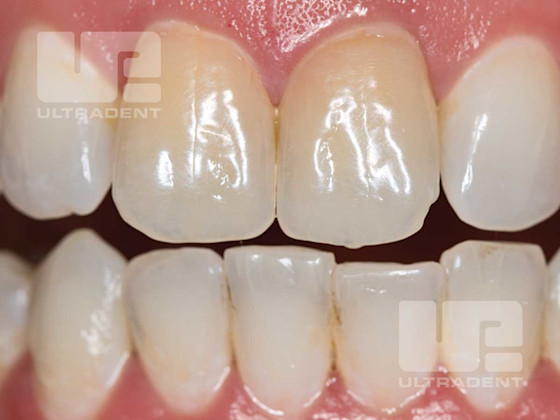

Before and After Opalescence Endo Non-Vital Whitening Gel

Before. (Photo courtesy of Dr. Rich Tuttle)

After. (Photo courtesy of Dr. Rich Tuttle)

Before.

After.

Before. (Photo courtesy of Dr. Arno Schoeler)

After. (Photo courtesy of Dr. Arno Schoeler)